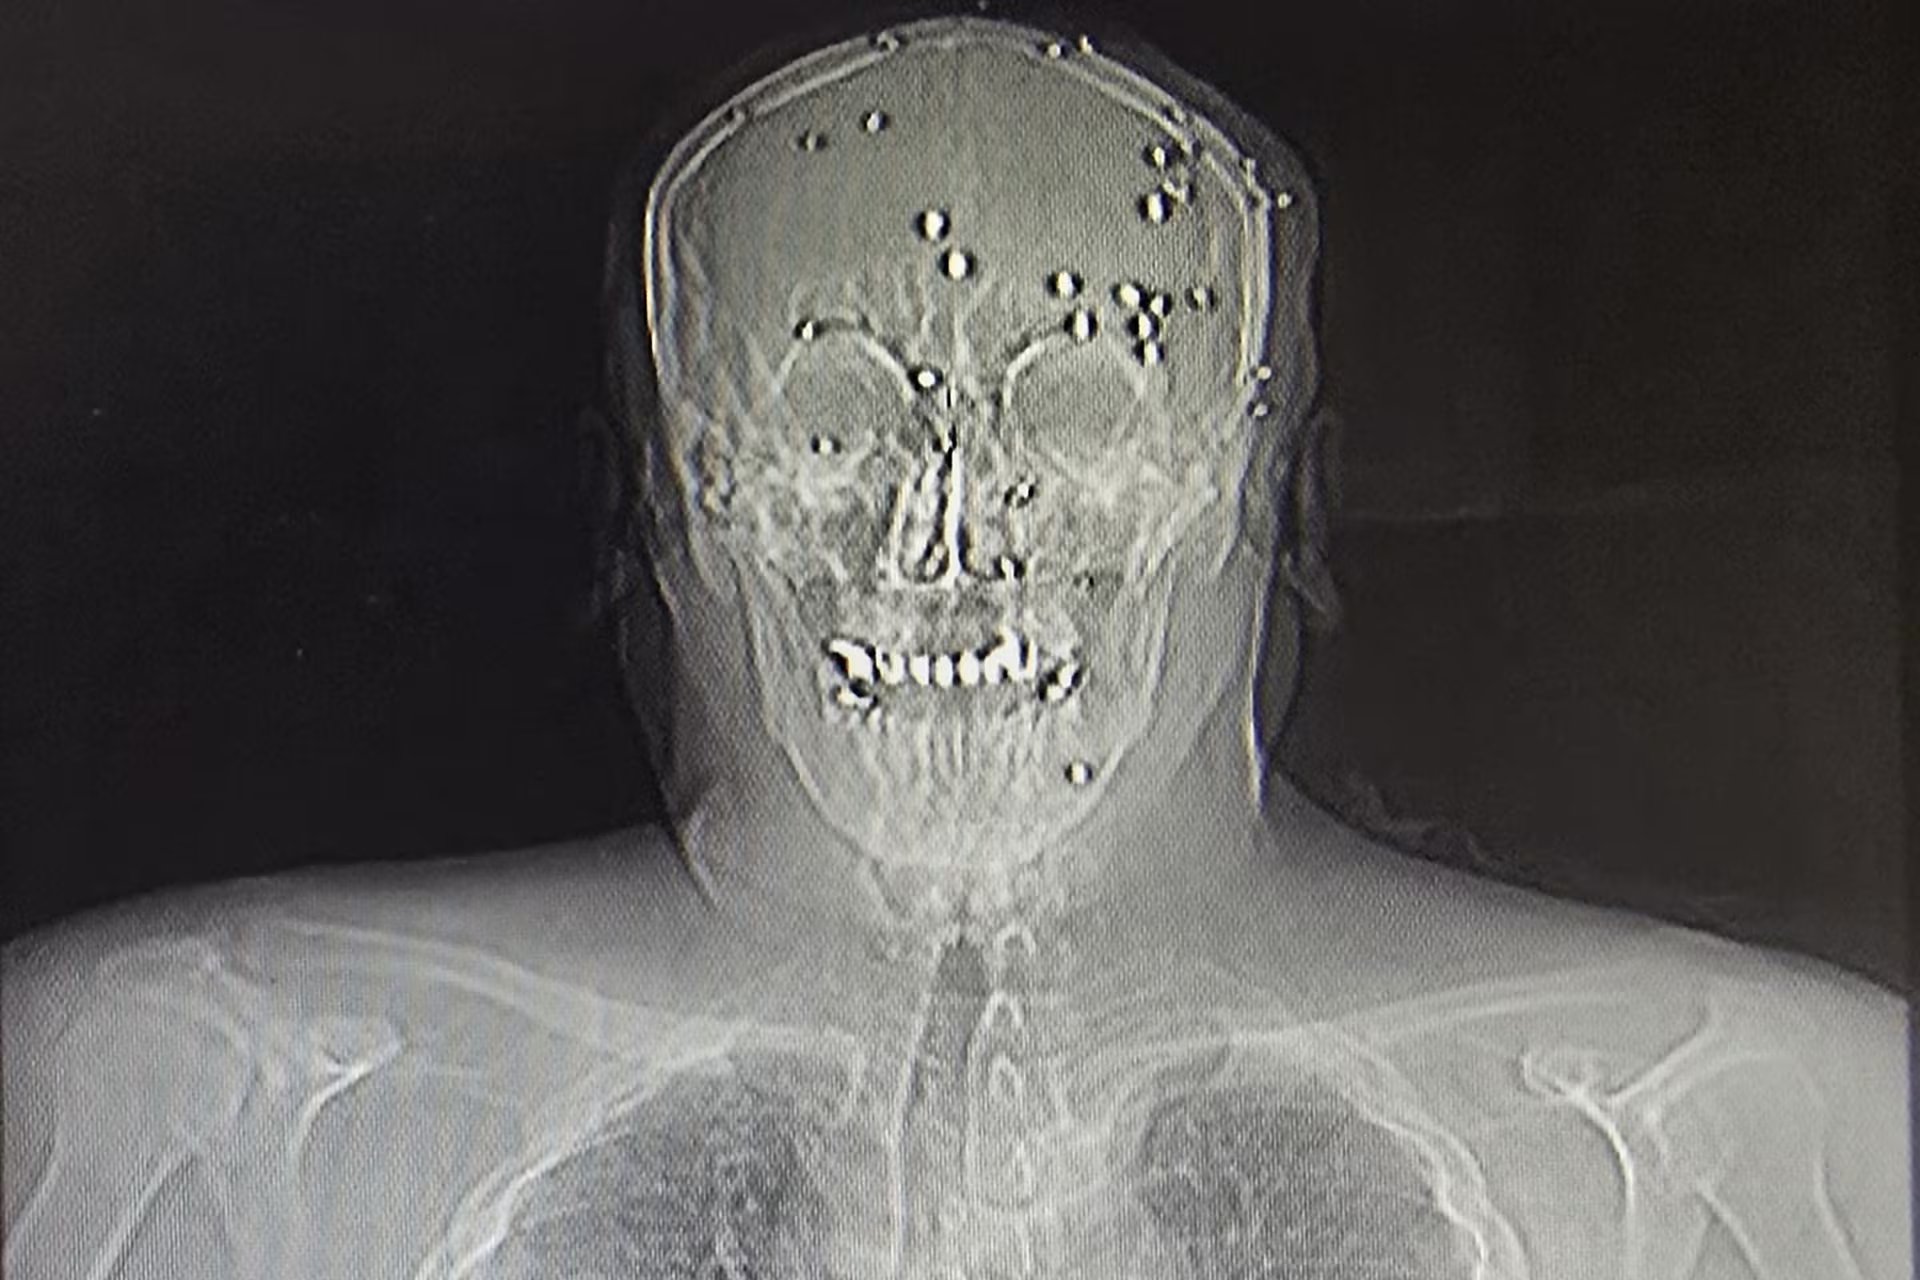

En medio de la intensa ola de manifestaciones que sacudió a Irán recientemente, los centros de salud se convirtieron en escenarios de alta tensión. Un médico joven en la localidad de Rasht relató cómo intentó socorrer a un hombre de unos 40 años que presentaba un impacto de bala a quemarropa en la cabeza. Mientras el equipo médico luchaba por reanimarlo, un contingente de agentes de seguridad armados, algunos vestidos de civil y portando fusiles, les impidió continuar con las maniobras de emergencia.

Tras el fallecimiento del paciente minutos después, los agentes procedieron a colocar sus restos en una bolsa negra para cadáveres, trasladándolos en una camioneta junto a otros cuerpos. Este suceso, lejos de ser un hecho aislado, forma parte de un patrón de intervención en los hospitales iraníes durante los primeros días de enero, donde se ha reportado la presencia constante de fuerzas represivas para vigilar a los heridos y detener a quienes participaron en las protestas contra la República Islámica, fundada hace 47 años.

Diversos testimonios de profesionales sanitarios coinciden en que la militarización de los hospitales ha alcanzado niveles sin precedentes en un país con un largo historial de represión. Informes de organizaciones de derechos humanos documentan casos donde las fuerzas de seguridad no solo intimidan al personal, sino que también retiran a pacientes de los respiradores y realizan detenciones arbitrarias dentro de las instalaciones médicas.

Por su parte, las autoridades gubernamentales han intentado desestimar estas acusaciones. Hossein Kermanpour, portavoz del Ministerio de Salud, calificó estas informaciones como falsas e imposibles, asegurando que la atención se brindó “sin discriminación ni injerencia política”. No obstante, la evidencia visual obtenida en lugares como el Hospital Imán Jomeini en Ilam muestra a agentes rompiendo puertas de vidrio y recorriendo pasillos armados, intimidando a los presentes.

La represión, que tuvo sus momentos más críticos los días 8 y 9 de enero, es considerada la más letal desde 1979. Aunque el régimen reconoce algo más de 3.000 fallecidos, organizaciones de activistas de derechos humanos afirman haber confirmado más de 7.000 muertes y continúan investigando miles de casos adicionales.